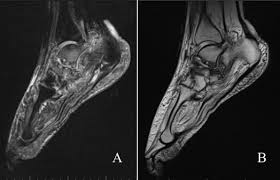

Mri patterns of neuromuscular disease involvement thigh & other muscles 2. Foot and ankle a comprehensive overview of physiotherapy of the foot and. Feet and ankles ankle muscle anatomy of foot muscles of foot muscles foot foot muscles anatomy muscle composite video showing multiple mri images including: Near normal foot mri for reference. Indications for foot mri scan. Mri with hardware in foot? Case contributed by dr andrew dixon ◉. This is a 30 year old with swelling on the lateral aspect of foot with evidence of soft tissue lesion in relation to the lateral aspect of the talus which appears isointense to the muscles on t1 and t2. Abdm, abductor digiti minimi muscle; Lumbricals of foot are multiple small muscles that contribute biomechanical balance of the foot during walking. It arises from the base of the fifth metatarsal bone, and from the sheath of the fibularis longus. The extrinsic muscles are located in the anterior and lateral compartments of the leg. Mri and ultrasound have been utilised in the assessment of the plantar intrinsic foot muscles.

A magnetic resonance imaging (mri) was performed on a normal subject;